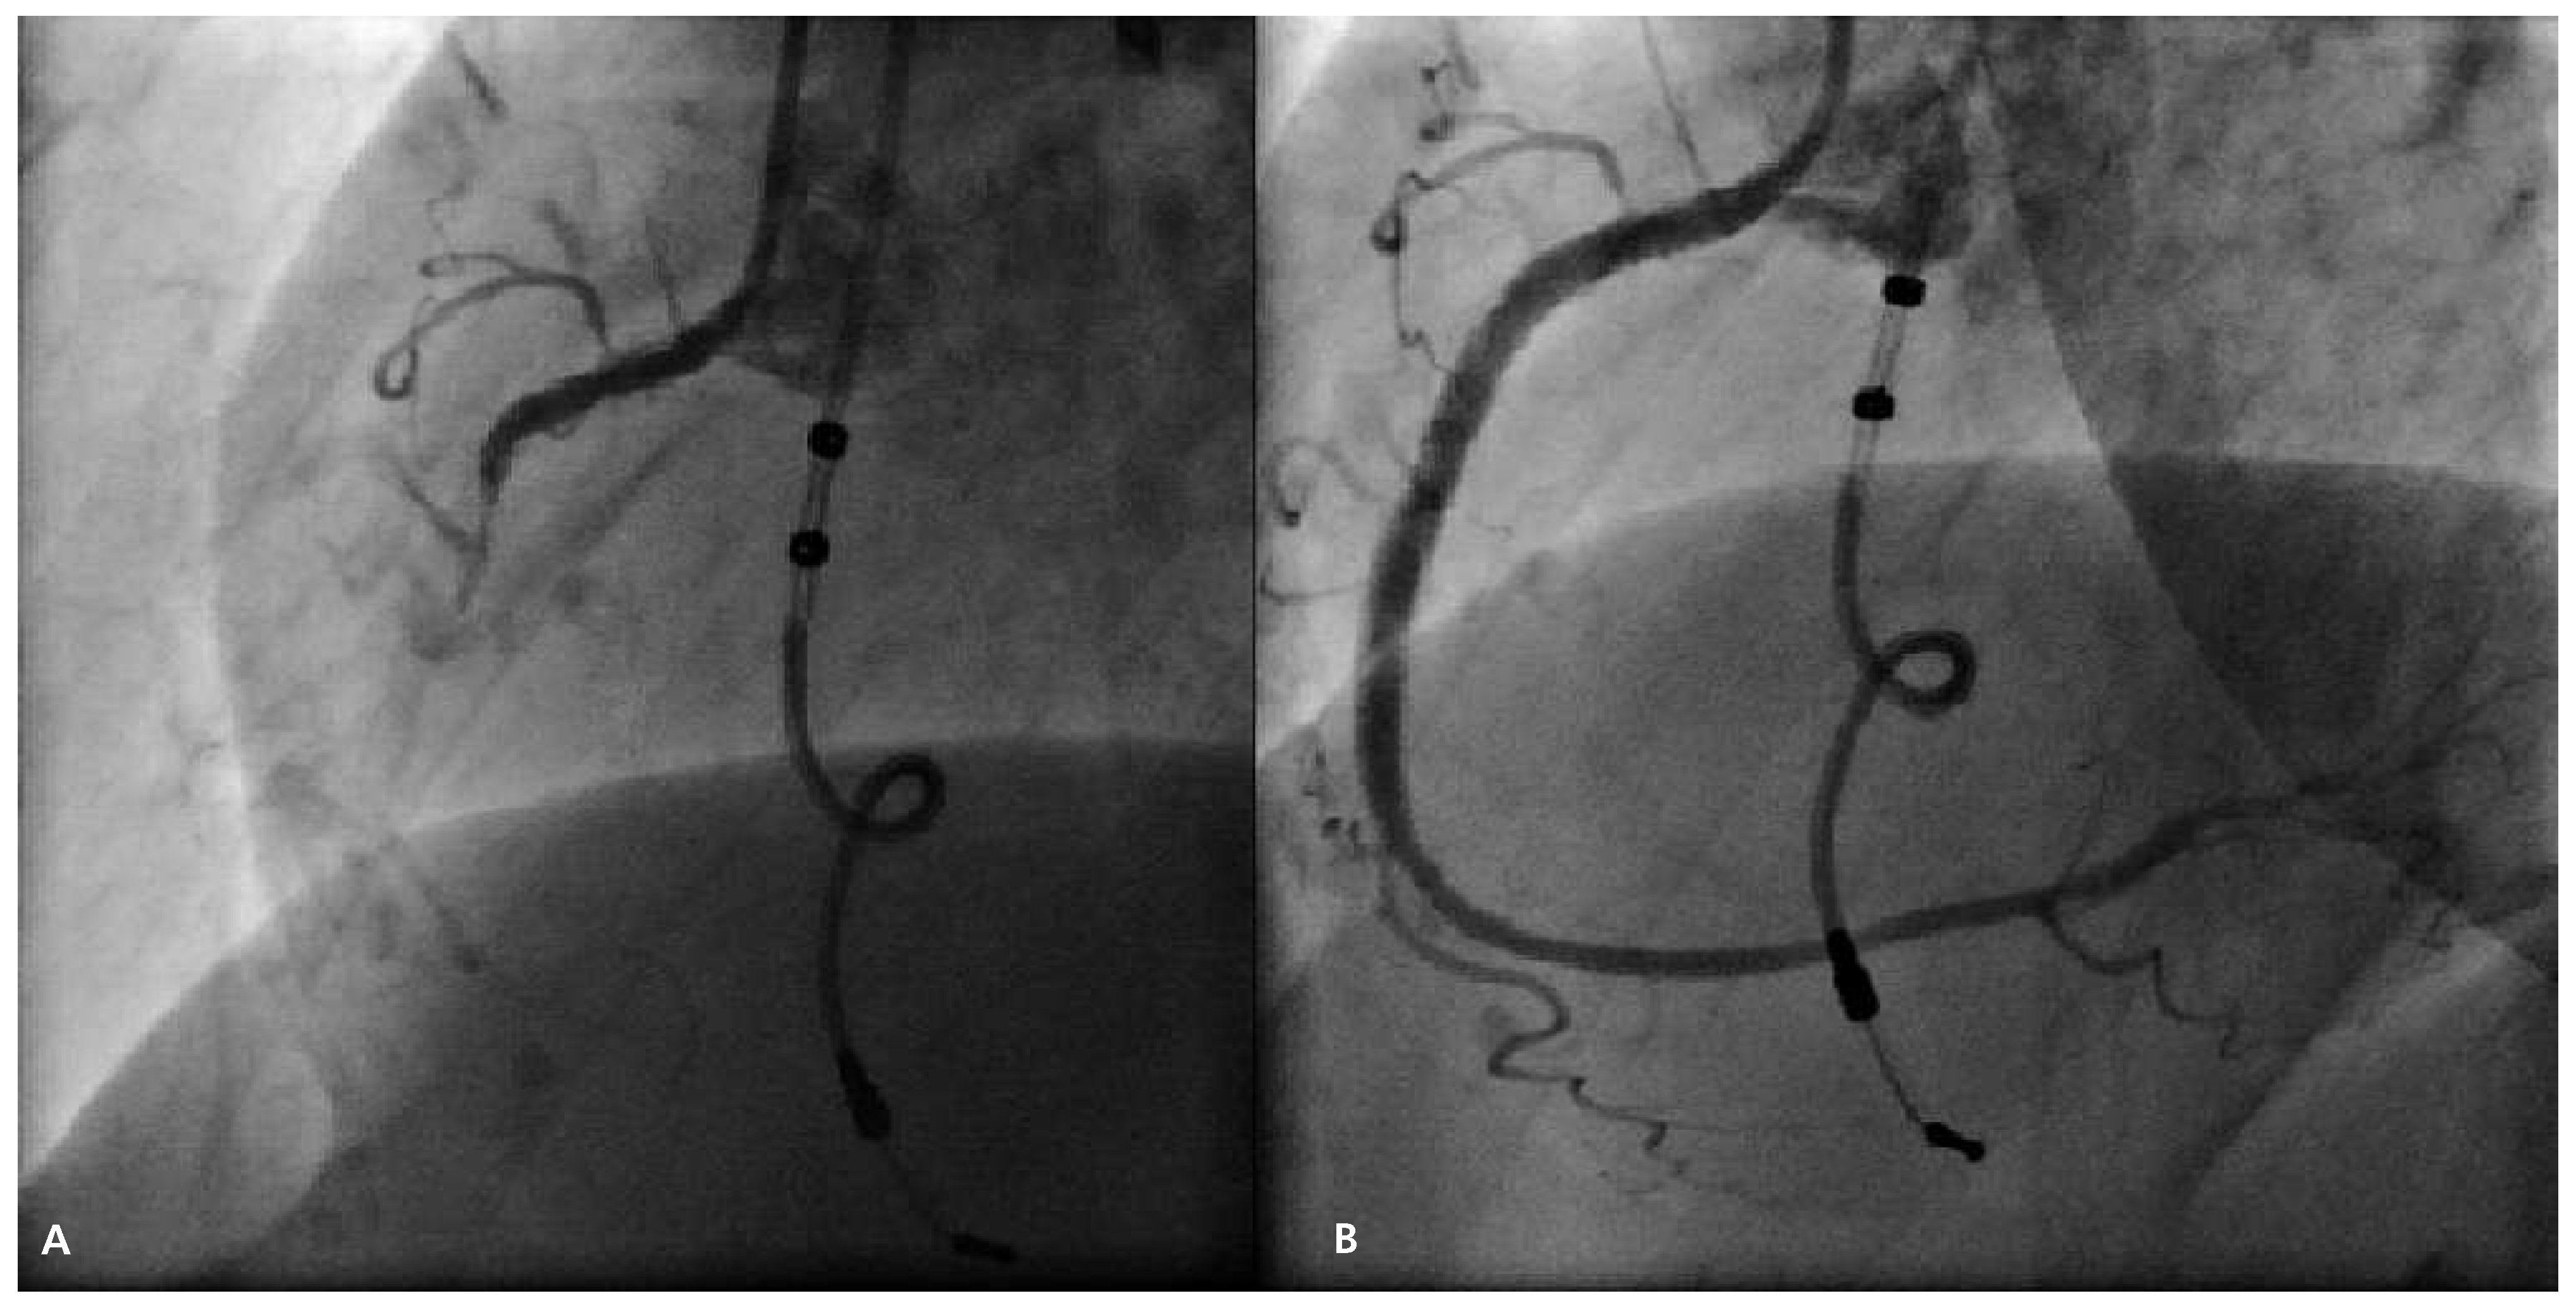

Criteria for diagnosing STEMI in patients with left bundle branch block were described by Sgarbossa et al. [1], but the criteria were published even before that for patients with a ventricular paced rhythm [2]. These criteria evaluate and score the following changes in the 12-lead ECG: ST segment elevation >1 mm concordant with the QRS in any lead (5 points), ST segment depression >1 mm in leads V1–V3 (3 points) and ST segment elevation >5 mm discordant to QRS in any lead (2 points). A score of more or equal to 3 was shown to have a specificity of >95% for STEMI, however, with a lower sensitivity. Recently, the criteria were further evaluated in 57 patients with ventricular paced beats and the most useful criterion was found to be ST elevation >5 mm discordant to the QRS complex [3]. Smith et al. published the revised Sgarbossa criteria resulting in a higher accuracy of the scoring system [4]. In their algorithm, the third step in the Sgarbossa criteria (>5 mm discordant ST elevation) is replaced by the proportion of ST/S changes in any lead. A ratio of peak ST segment elevation compared to the S wave <–0.25 indicates acute myocardial infarction. In our patient, two of three criteria were present using the original Sgarbossa criteria (total score: 5 points), and the ST/S criterion was also indicating STEMI. Another option for diagnosing STEMI in patients with ventricular paced beats is either evaluating spontaneous beats, if present, or temporary discontinuation of pacing [5]. However, this can be misleading due to changes of repolarisation after ventricular pacing is discontinued (cardiac memory) [6]. Also, it requires adequate equipment and personnel trained in using pacemaker programmes. Since the patient first presented to a regional hospital, the indication for the transfer to our institution for primary PCI had to be made on the basis of the clinical presentation and the presented 12-lead ECG. On the basis of the ECG criteria mentioned above, the diagnosis of STEMI was made and the patient was transferred for primary PCI. Another finding on the 12-lead ECG was the loss of the “tracking” function of the VDD pacemaker. Loss of atrial sensing has been described in up to 20% of patients with VDD pacemakers [7]. We can only speculate whether loss of sensing was due to atrial infarction in our patient. Potential reasons for loss of atrial sensing in myocardial infarction could be right ventricular dilatation due to myocardial ischaemia with inferior displacement of the sensing dipole or acute atrial ischaemia and infarction with decrease in atrial signal amplitude. As seen in (Figure 2), some of the RCA branches were occluded at the time of presentation. Since undersensing persisted after early revascularisation, we assume that this finding is coincidental and is due to chronic loss of atrial sensing, but an association with the infarction cannot be ruled out.

Management

Figure 2. (A) Coronary angiography showing occlusion of the proxymal RCA. Also lead of VDD pacemaker can be seen. (B) Coronary angiography after PCI of the RCA.